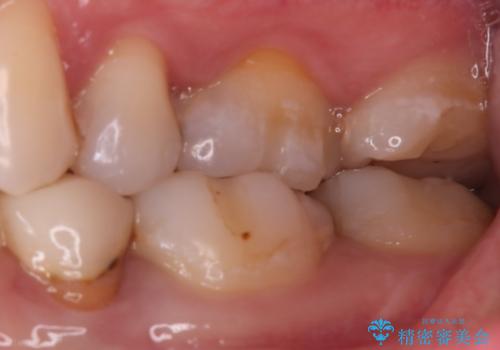

- 奥歯に虫歯があると言われて治療された患者様です。

何度か同じ歯に保険治療で治したそうですが、欠けたり再度う蝕になってしまった経験から自費治療を希望され、丈夫でキレイなセラミッククラウンにて治療いたしました。